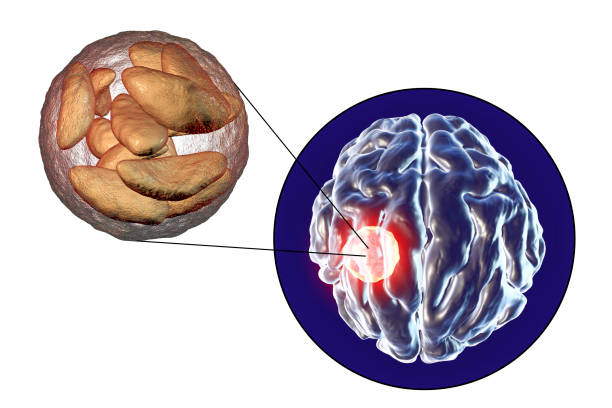

✅뇌경색 후유증 종류

뇌경색 후유증은 다양한 증상을 유발할 수 있습니다. 이러한 증상은 흔히 다음과 같이 나눌 수 있습니다.

4. 뇌관 부위 손상

뇌관은 우리 몸의 생체 징후를 담당하는 부위로, 이상이 있는 경우 음식을 적절히 소화하지 못하게 되어 식사에 어려움을 겪을 수 있습니다. 호흡 장애도 발생할 수 있어 인공호흡 장치가 필요할 수 있습니다.